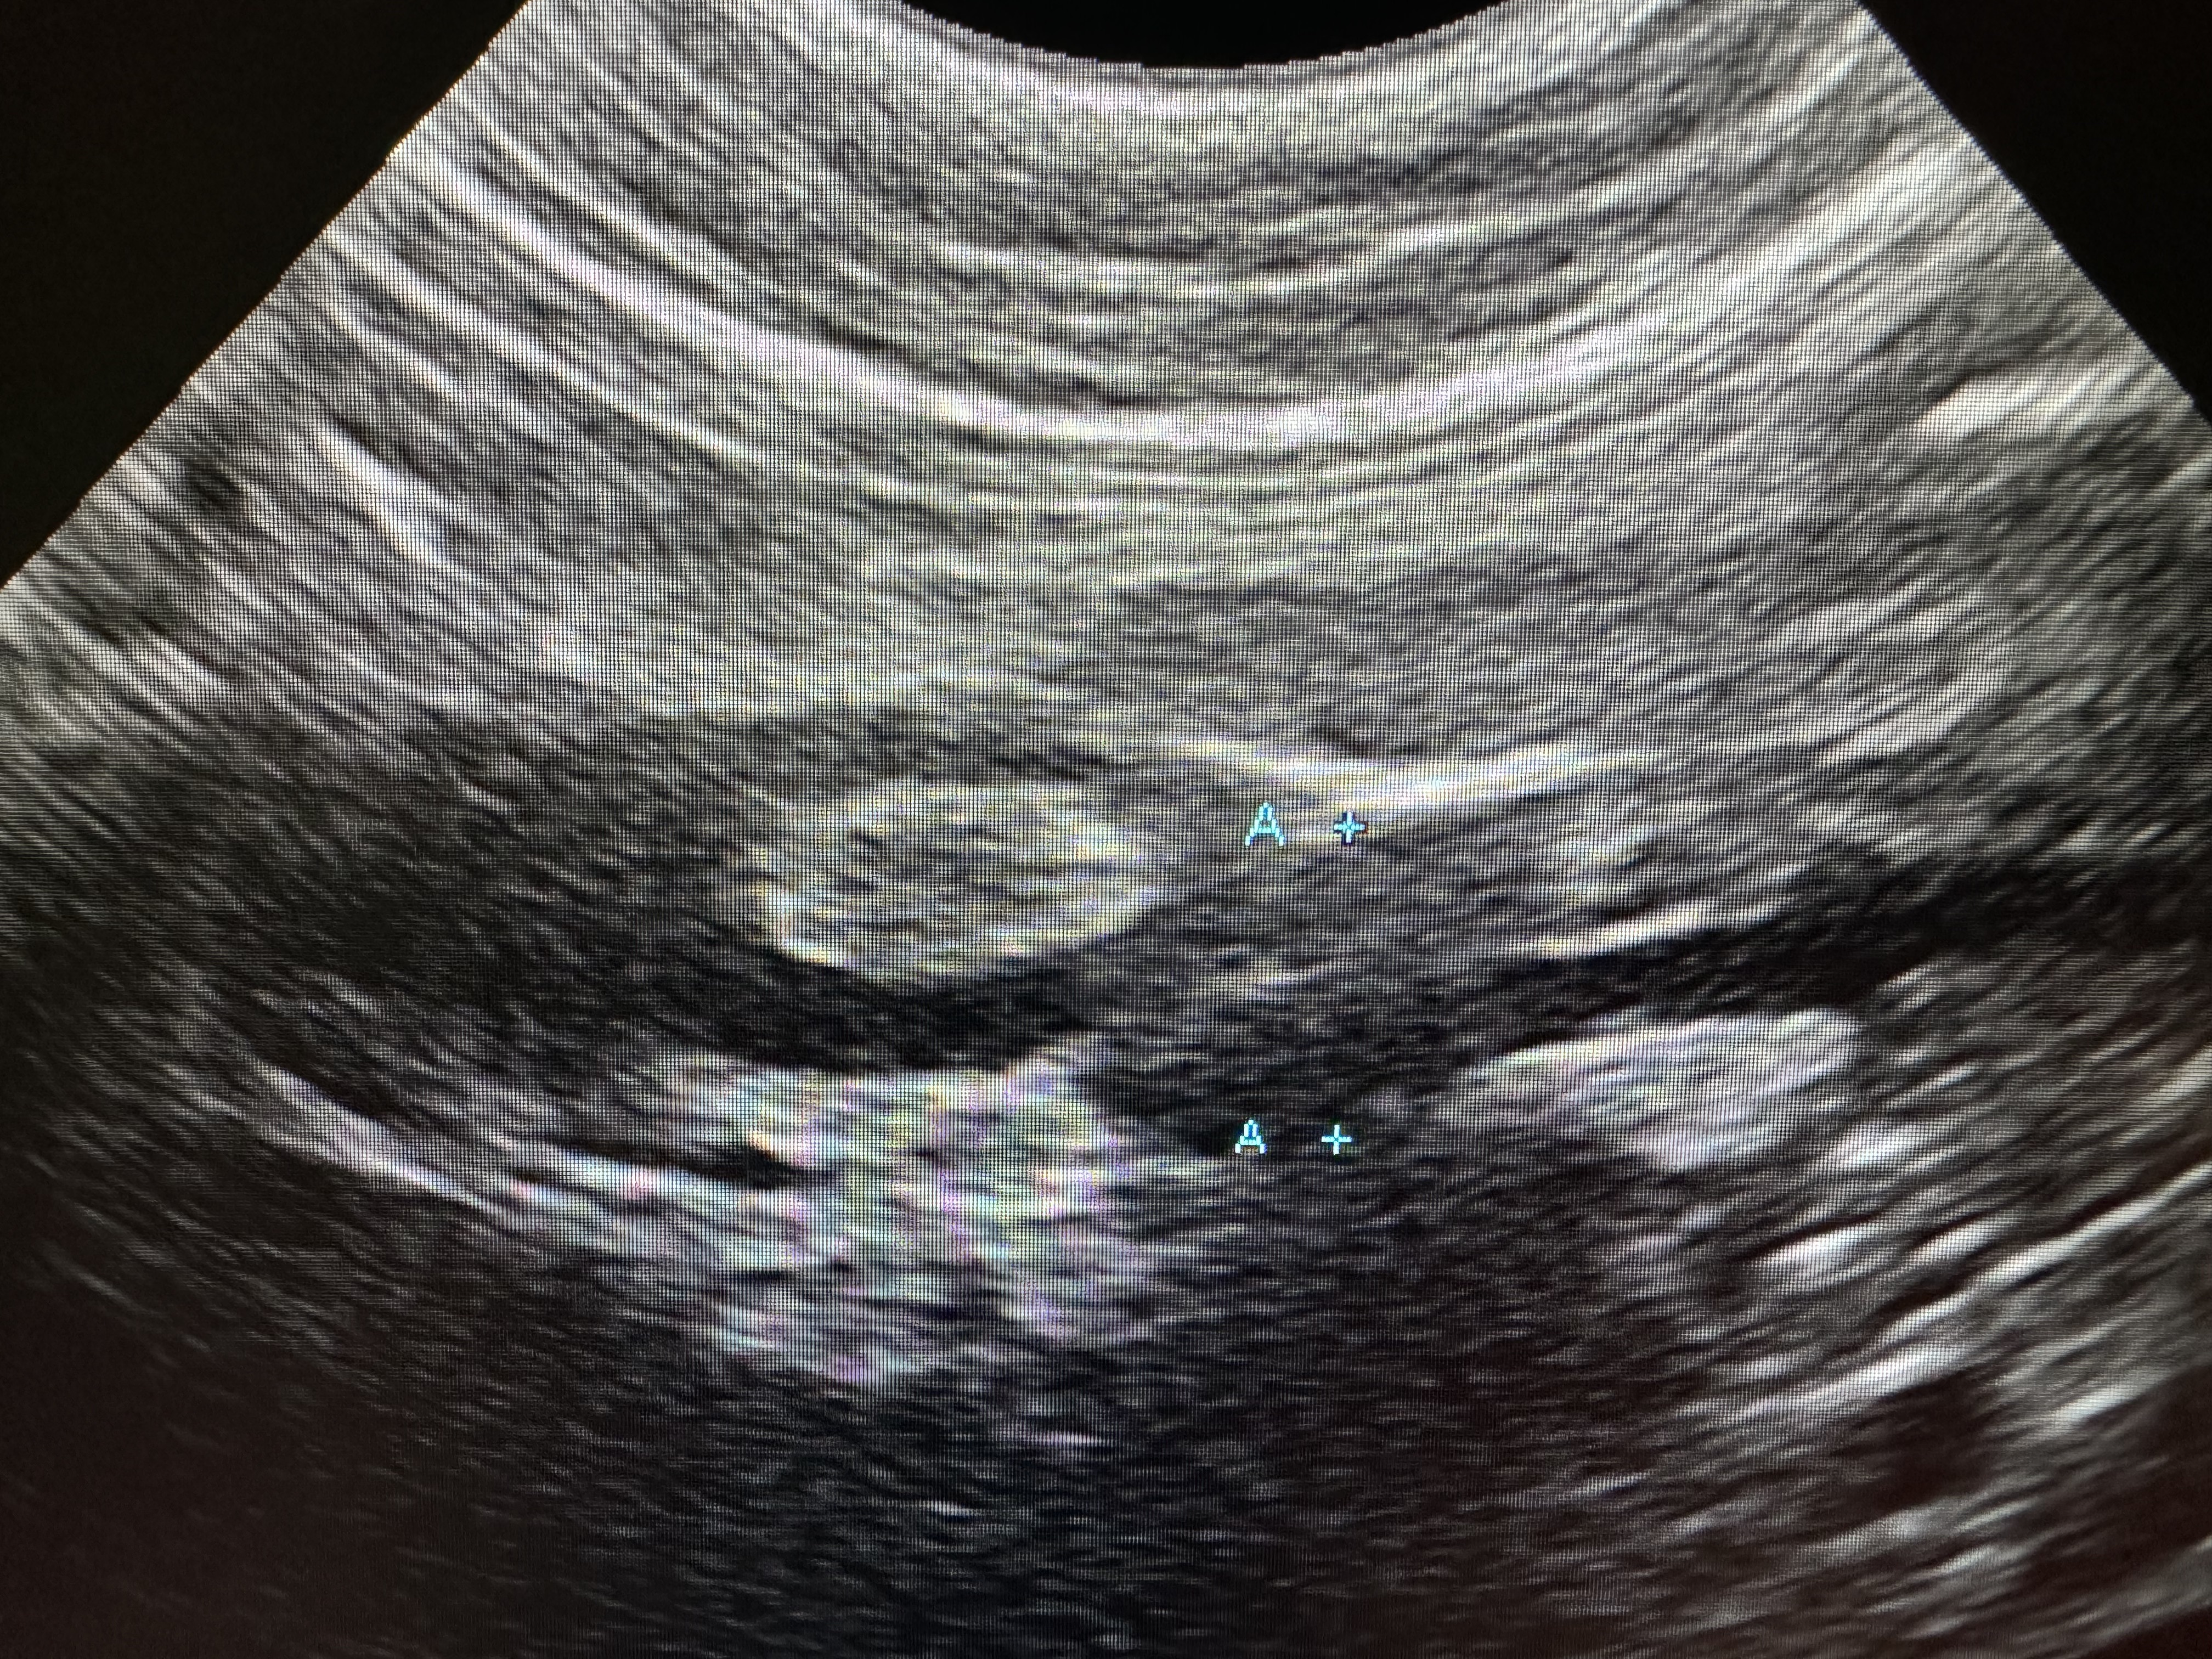

IBDまたは小細胞性リンパ腫が疑われた猫ちゃんの小腸と腸間膜リンパ節(と思われる)の腹部エコーの写真です。左側に輪切りで見える小腸の壁が厚くなっています(特に筋層と呼ばれる外側の黒い領域)。その横に黒く楕円形の組織も認められ、腸管膜リンパ節が腫れていることが疑われます。このような事例は通常病理検査でIBDか小細胞性リンパ腫か診断をつけて、主にステロイドで治療を行うことで症状が改善します。IBDと小細胞性リンパ腫では存命期間に違いがあり、後者の方が重症であることが多いようです。